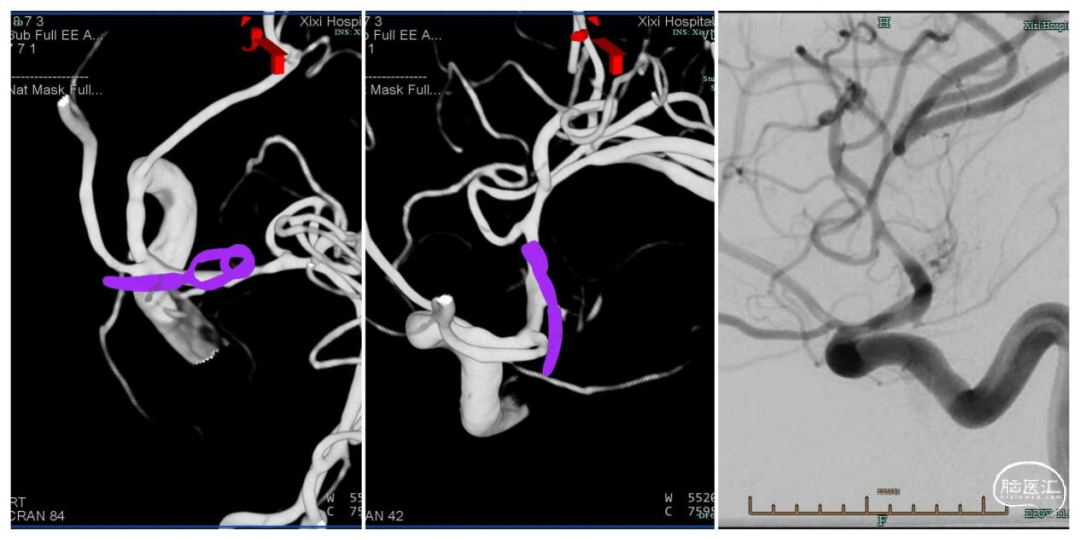

图3. DSA模拟手术体位

术后12天复查造影:动脉瘤夹闭完全,无明显残留,载瘤动脉远端有轻度狭窄(图5)。